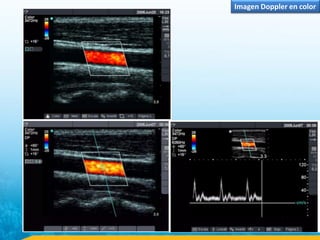

Imagen Doppler en color